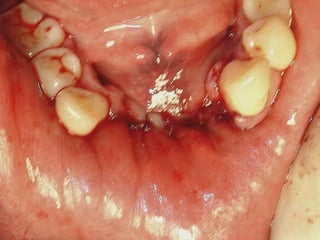

Eliminación de focos sépticos en bloque en paciente con osteitis

mandibular crónica

Osteitis

Imagen microscópica de osteitis, inicialmente existe una etapa de

osteoclastosis seguida por regeneración. No siempre el hueso

regenera en su totalidad y sigue el curso de cualquier inflamación

dejando un area de tejido fibroso que con el tiempo puede

calcificarse (hueso denso)

Manejo con antibióticos obligado

Revisión periódica